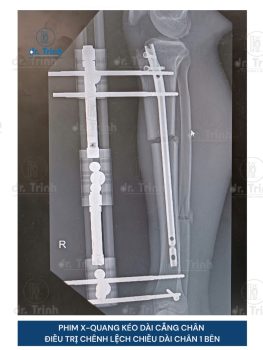

Xem thêmPHẪU THUẬT KÉO DÀI CHÂN – NÊN KÉO ĐÙI HAY KÉO CẲNG CHÂN?

Phẫu thuật kéo dài chân đã trở thành một giải pháp phổ biến cho những...